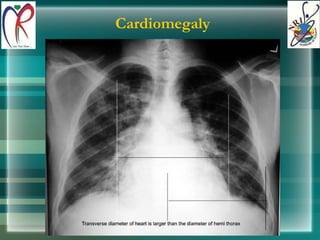

Cardiomegaly